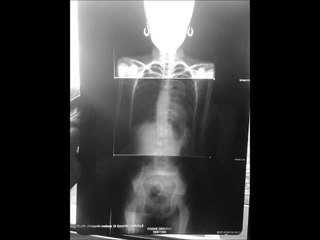

Latest Scoliosis Statistic and New Scoliosis Treatment the ELIMINATES bracing or surgery!

Don't just be a statistic!br Take control of your spine and health today!br